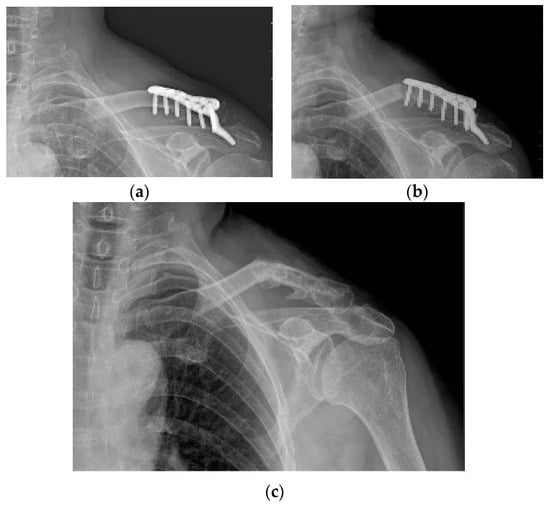

Figure 6. The only case of non-union among five incomplete union cases. (ac) A 50-year-old male patient is fixed with a hook plate and bone union is not completed at 4 months, but severe painful shoulder stiffness is noted; therefore, manipulation is performed while removing the metal plate. (d) Bone union does not occur during the follow-up period.

Varying degrees of subacromial erosion occurred in all patients, and acromial fracture occurred in one case in the DCF group and seven cases in the ACD group (Figure 2 and Figure 3). Five (6.7%) cases showed incomplete union and one (1.3%) case showed peri-implant stress fracture in the DCF group (Figure 4 and Figure 5). Four of the five cases of incomplete union showed fracture union without additional surgery during the follow-up period, and one case did not heal at the final follow-up, although the patient did not show any discomfort with non-union (Figure 6). The peri-implant fracture healed with conservative management before plate removal. LOR was observed in nine patients with ACD. Before removing the hook plate, LOR occurred in six patients with ACD. Among these six patients, five showed acromial fracture and one showed serious subacromial erosion (Figure 7). After removing the hook plate, LOR occurred in three patients during the follow-up period. However, none of these patients with LOR among patients with ACD showed tenderness on the acromioclavicular joint or pain during the follow-up period. Regarding acromial fracture, one (1.3%, 1 of 36) case was observed in the DCF group and seven (8.3%, 7 of 33) cases were noted in the ACD group (Figure 4). There was no difference in the incidence of acromial fracture between patients with DCF and ACD (p = 0.066). All eight patients had fracture union without additional surgical treatment during the follow-up period.

As a rare complication after hook plate fixation, incomplete union in DCF cases and acromial fracture in DCF and ACD cases were observed in our study. The incidence of incomplete union or non-union in the DCF group was 4% in a study by Tiren et al. [19], 5% in a study by Good et al. [11], and 0% in a study by Lee et al. [41]. In our study, incomplete fracture union occurred in 6.7% of patients, and no patient complained of pain or tenderness and underwent additional surgery for bone union during the follow-up period after metal plate removal. In terms of the risk factor for PSS, incomplete union in DCF cases was not related to the incidence of PSS (Table 3).